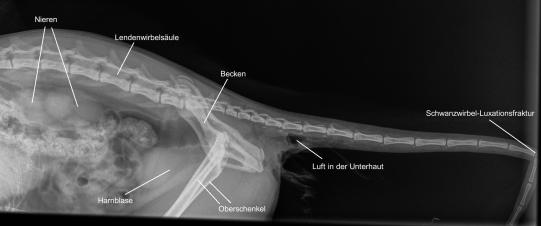

Da davon ausgegangen werden muss, dass Cali verunfallt ist, wird ein Röntgenbild der Lunge angefertigt - häufig sind Lungenrisse oder -blutungen Folgen eines Autounfalles. Die Lunge ist aber glücklicherweise unversehrt, dafür zeigt sich im Röntgen des Becken-Schwanzbereichs dass die Katze eine Luxationsfraktur des Schwanzes (sowohl Ausrenkung eines Schwanzgelenkes als auch Bruch eines Schwanzwirbels) zugezogen hat und durch die Wunde an der Schwanzunterseite Luft in die Unterhaut gelangt ist.

In Narkose wird der Schwanz ausgeschoren. Nun wird ersichtlich, dass dieser schwer beschädigt worden ist - durch Zugkraft wurde die Schwanzwirbelsäule im hinteren Drittel gebrochen und luxiert; zu allem Unglück ist auch die Haut an der Schwanzwurzel-Unterseite vom Körper abgerissen - hier klafft nun eine diffus blutende Wunde. Durch das Reissen an der Haut ist diese offenbar auf der ganzen Länge nicht mehr richtig durchblutet und fühlt sich kühl an. Als positiv kann gewertet werden, dass einige Millimeter Haut um den After und der After selbst unverletzt scheinen.